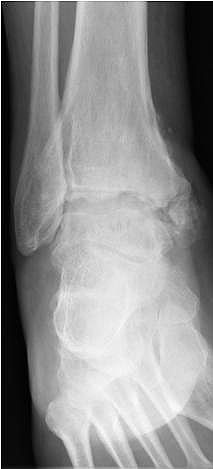

• Primäre oder posttraumatische Arthrose des OSG und USG (Abbildung 1, Abbildung 2).

• Revision einer gescheiterten Fusion des OSG/ USG (Abbildung 3, Abbildung 4).